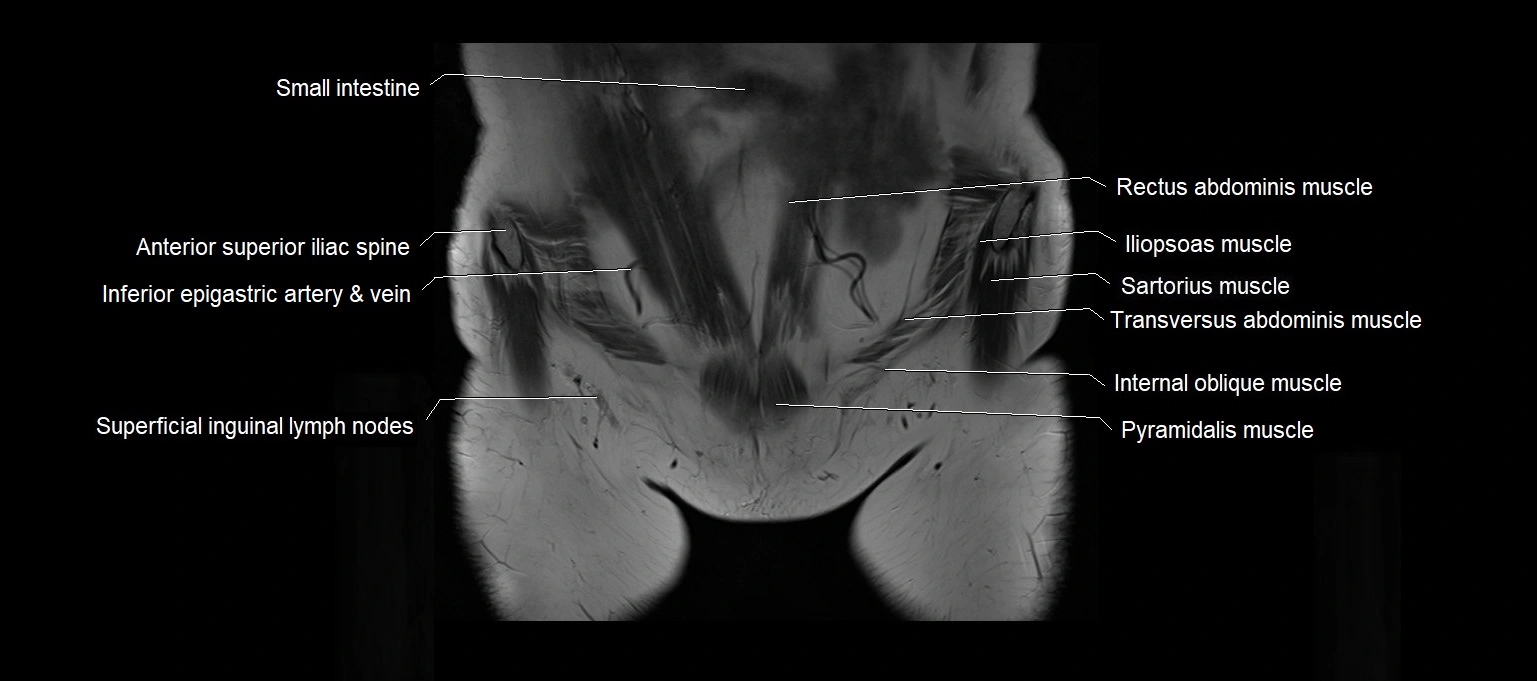

- Anterior superior iliac spine

- Iliopsoas muscle

- Inferior epigastric artery

- Inferior epigastric veins

- Pyramidal muscle (pyramidalis muscle)

- Sartorius muscle

- Superficial inguinal lymph nodes

- Transverse abdominal muscle